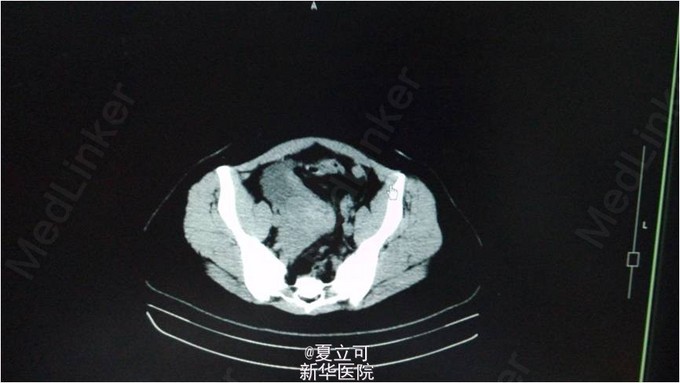

患者,女,21岁。患者1月无明显诱因下出现阵发性左下腹痛,疼痛为刺痛,伴有纳差、恶心感,无呕吐,无发热、腹泻、反酸等。 查体:腹平软,脐周偏左压痛,无反跳痛及肌卫,肝脾肋下未及,移动性浊音阴性,肠鸣音正常。 辅助检查:血常规:CRP 38mg/L,白细胞计数 10.21 10^9/L,肝肾功能、电解质、心肌酶谱、肿瘤指标均未见明显异常。 诊断:左卵巢浆液性囊腺瘤伴出血坏死 治疗过程及结果:入院后1天,患突发全腹疼痛,伴有大汗、心悸不适,当时心率103次/分,血压138/85mmHg。查体:腹紧张,压痛,腹部可及巨大包块,质软。急查腹部CT平扫:腹盆腔巨大囊性占位。阴超:巨大盆腹腔囊性包块,宫底部前方实性包块,腹水。腹部MRI:左下腹及盆腔可见巨大囊性病灶,大小约19*13*23cm。考虑左侧卵巢来源囊腺瘤。后于全麻下行腹腔镜探查+腹腔镜左附件切除+粘连松解术,术中冰冻:左卵巢浆液性囊腺瘤伴出血坏死。术后抗炎补液等对症支持治疗后,症状好转出院。 随访一个月未在出现腹痛症状。 经验:该患者为年轻女性,以反复左下腹痛入院,除消化道疾病外还需考虑妇科疾病,如宫外孕、卵巢囊肿等。该患者虽外院检查提示妇科超声未见明显异常,但最终证实为卵巢囊肿蒂扭转,故提示在临床工作中,不能过分依赖辅助检查,仍应以对病人临床症状观察为主导,结合相关辅助检查协助诊治,必要时复查相关检查十分重要。该病例诊治过程中处置及时,故预后好。